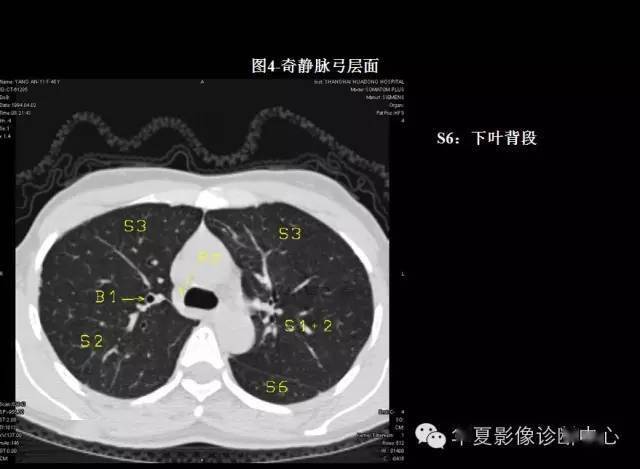

本文来源:华夏影像诊断中心 掌握肺部疾病ct,快速学好肺部感染ct,so